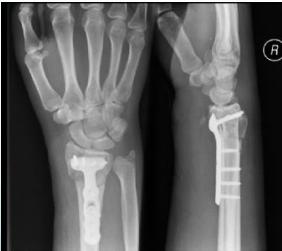

Buttress Plate (T-Plate/L-Plate):

- Indications:

- Lateral or medial tibial plateau fractures

- Distal radius fractures

Anatomical Plates with Locked Screws:

- Indications: Metaphyseal fractures

- Advantages:

- Anatomically contoured

- Very good fixation in metaphyseal area and osteoporotic bone